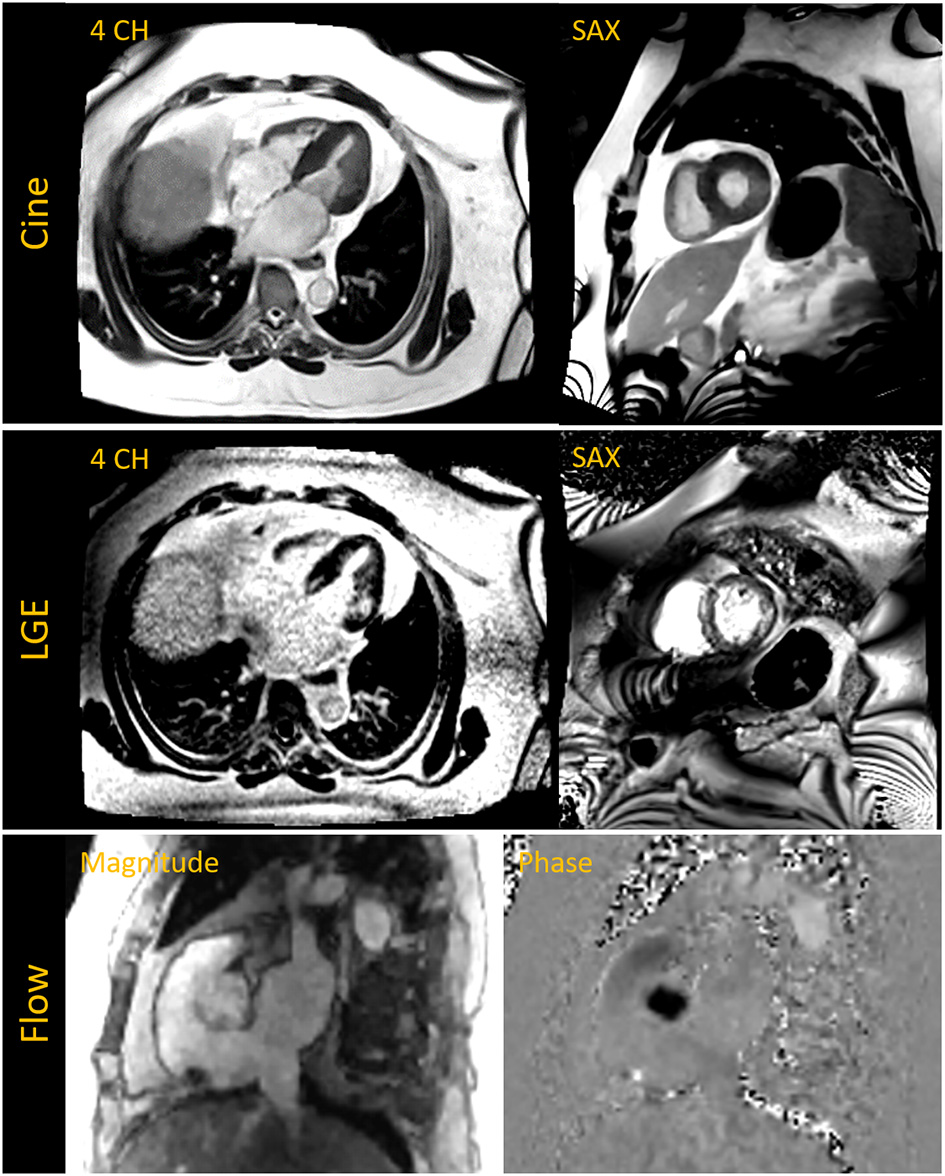

Figure 10

The top row shows breath-held segmented compressed sensing (CS) based cine images acquired in the four chamber (4 CH) and short axis (SAX) view in a patient with a BMI of 57 kg/m2 and who was previously unable to complete a cardiac MR exam on a 70 cm bore system. Late gadolinium enhanced (LGE) images in the middle row depict fibrosis on the septum and lateral wall. The 4 CH was acquired with a free-breathing motion-corrected (MOCO) LGE sequence while the SAX image was acquired with a breath-held segmented method. The bottom row shows magnitude and phase images of the aortic root acquired with a CS based 2D phase contrast cine for flow assessment.